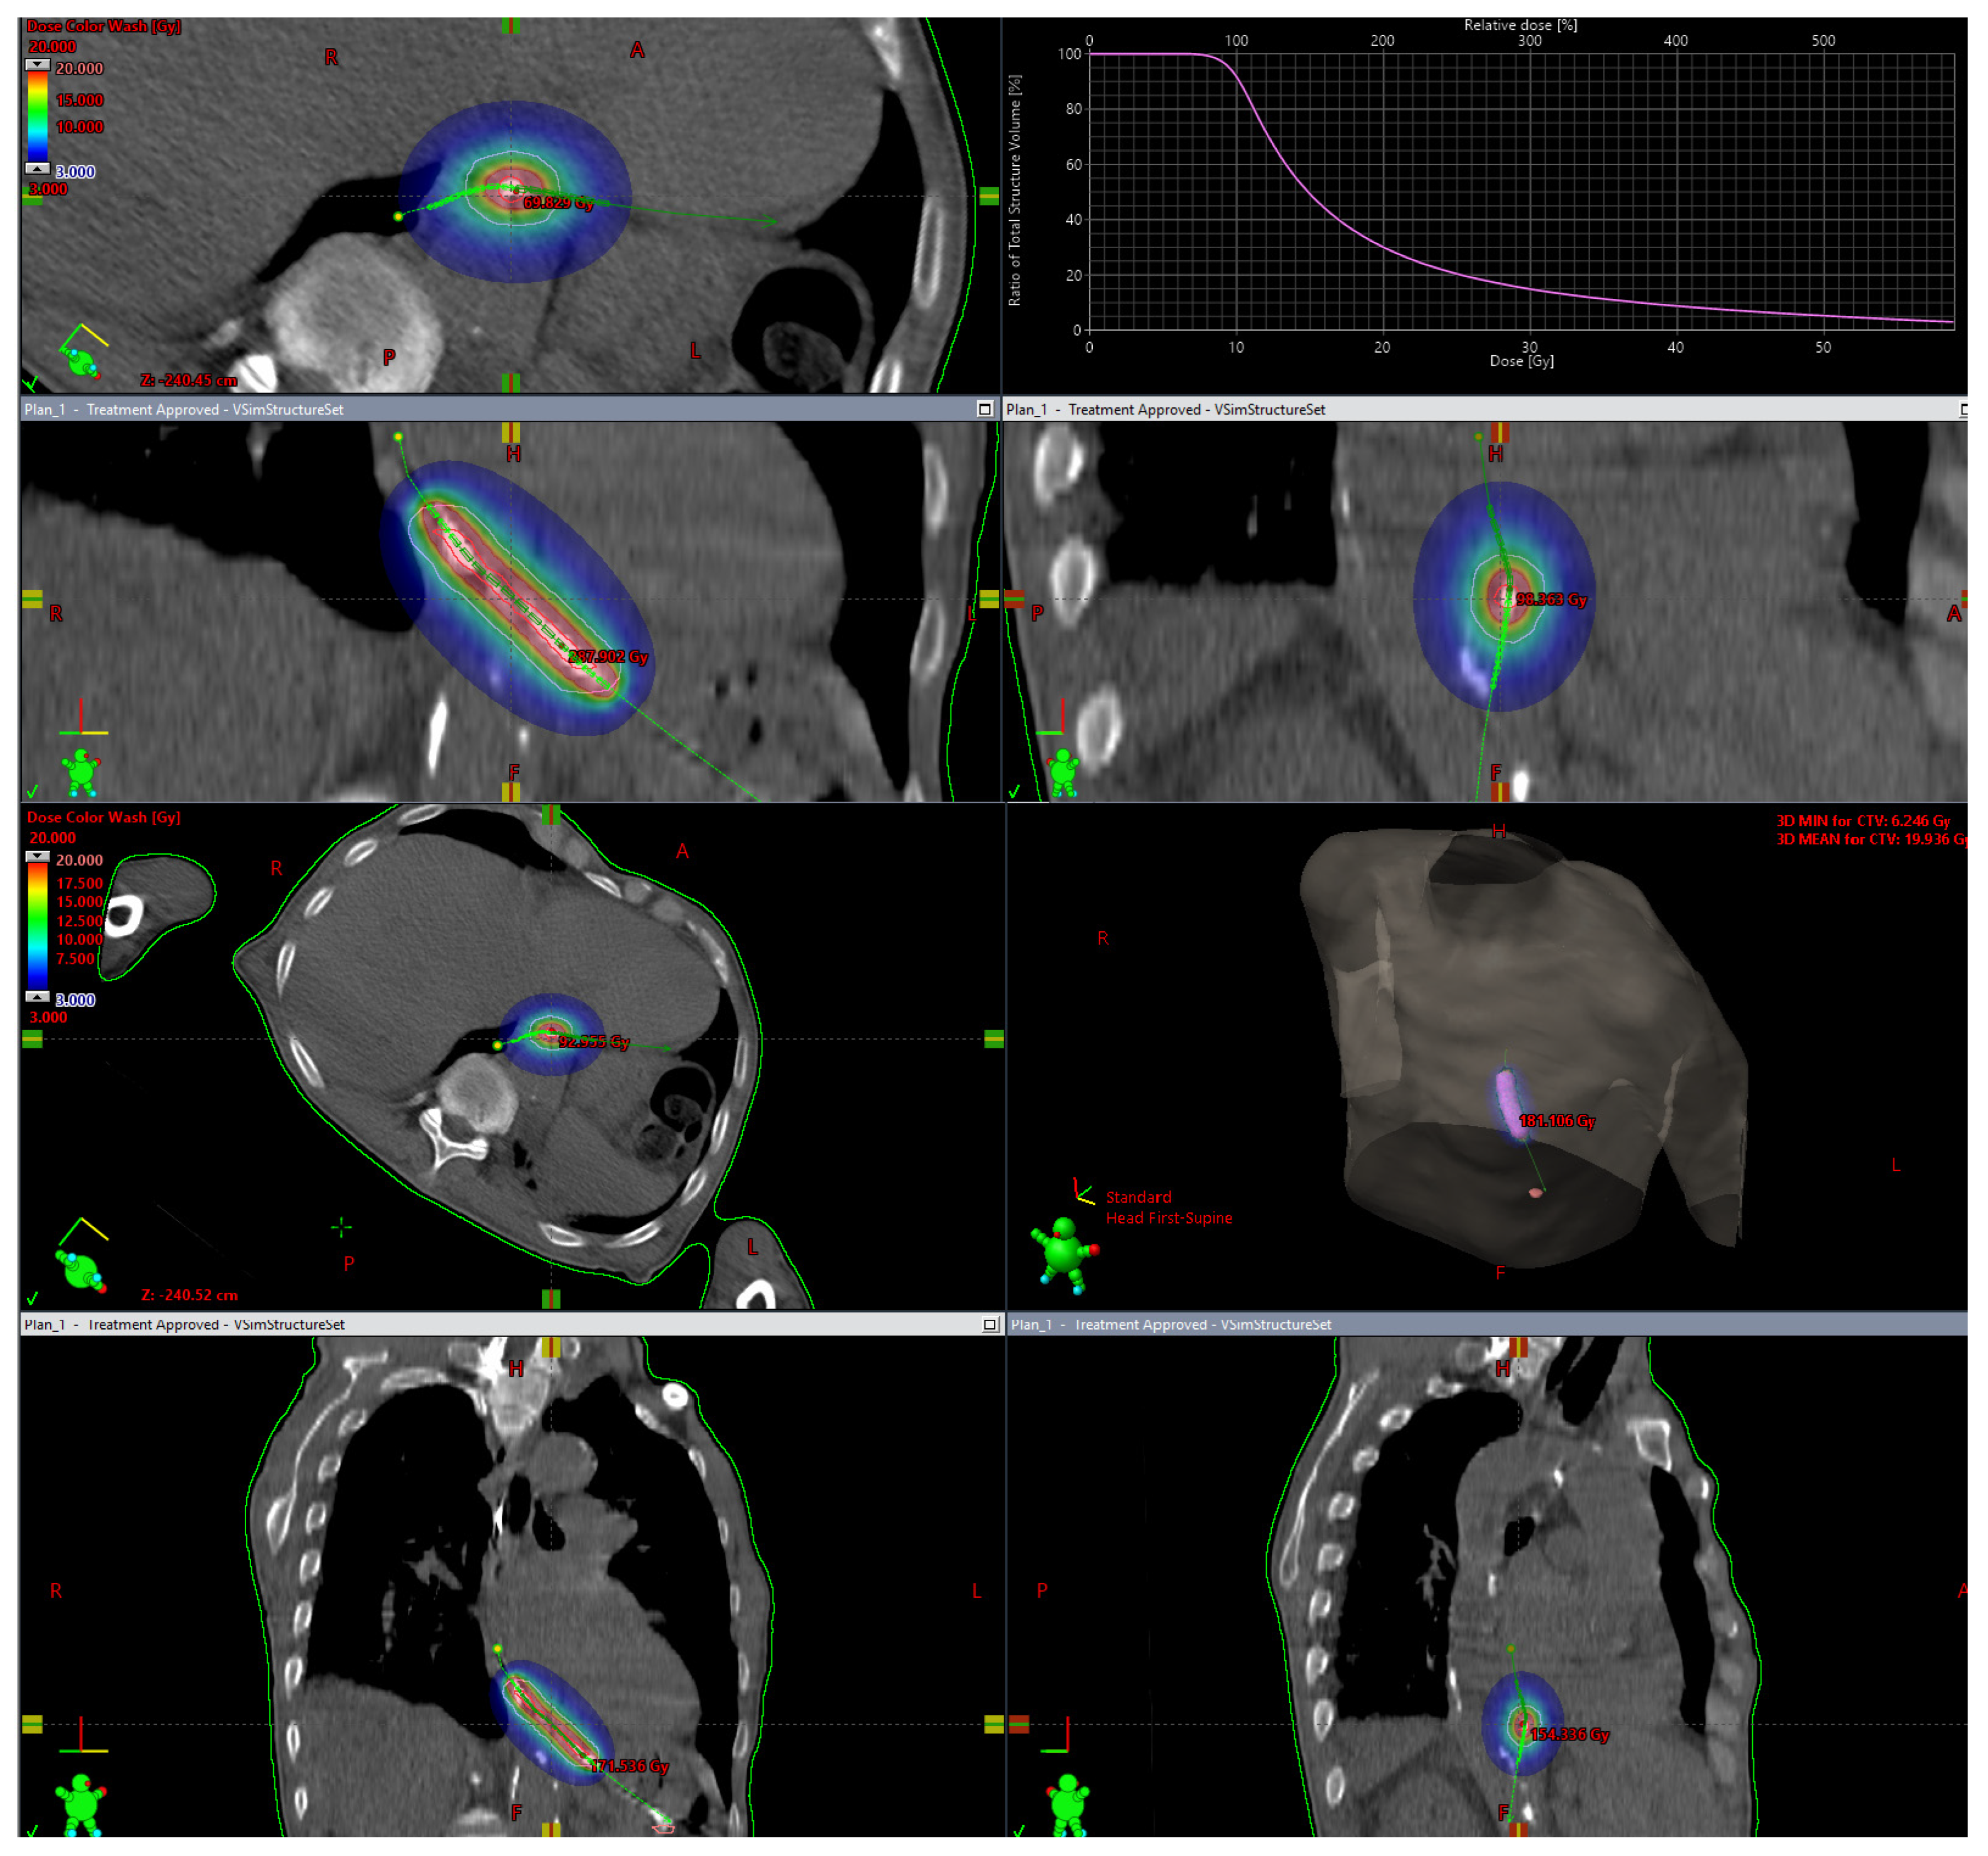

2. Brachytherapy as Radical Treatment

3. Brachytherapy Combined with Teleradiotherapy in Advanced, Non-Operative Stages